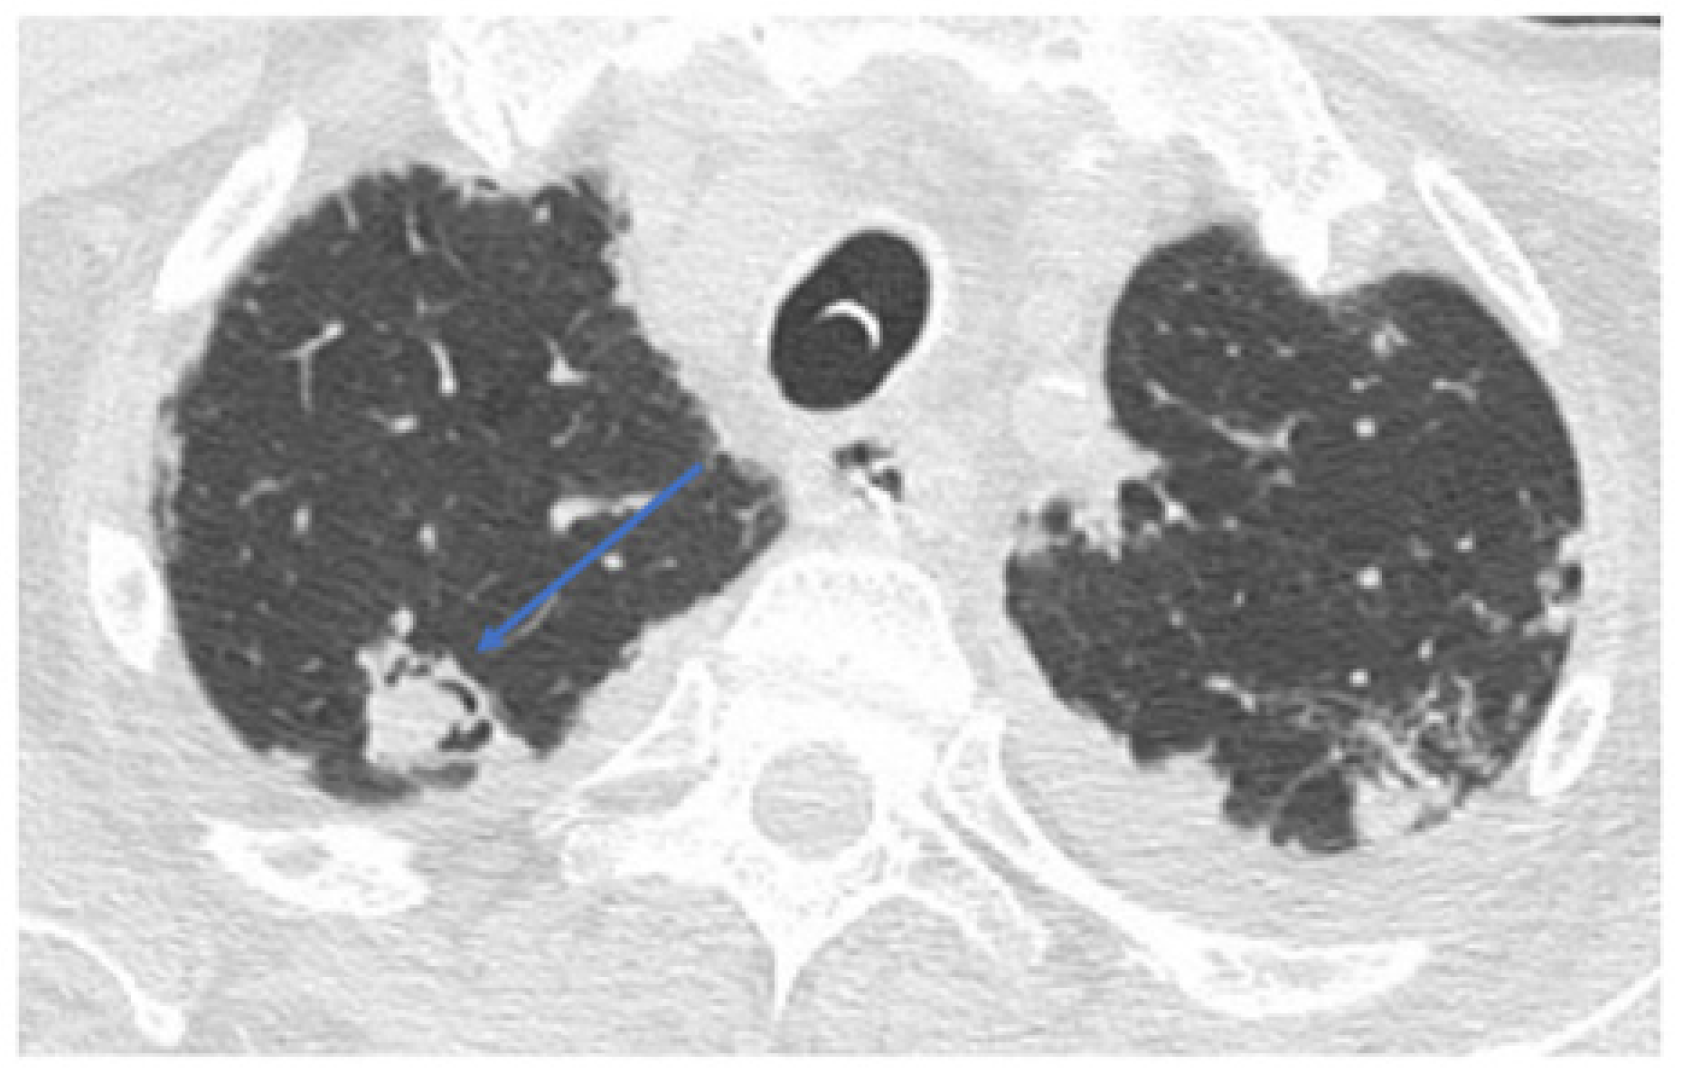

Eight weeks after hospital discharge (day 127), the patient returned to the ED with massive hemoptysis. He was in severe respiratory distress and hypoxemic (SpO2 90% with 100% oxygen mask). His blood tests showed mild anemia (Hb 9 mg/dL) and an increased C-reactive protein. The patient’s conditions required invasive mechanical ventilation through a tracheostomy. A fiberoptic bronchoscopy was performed to clean airways from bright red blood clots. An obstructive and active bleeding lesion in the left main bronchus was identified, as shown in the video clip (Supplementary Material). Serum β-D-Glucan was 1.49 ng/mL (normal values < 0.08 ng/mL), and the Galactomannan index in BAL was positive. BAL tested positive for Aspergillus flavus. Microbiological findings from BAL are shown in Figure 1. A chest CT scan performed in the emergency department showed a complete collapse of the left upper lobe and lingula and partial collapse of the left lower lobe, with main bronchial branches obstructed by clots (arrow in Figure 2A). A pseudo-aneurysm was also found in the upper anterior left lobe (arrow in Figure 2B).

Figure 2.

Chest CT scan at emergency department admission. Legend: complete collapse of left upper lobe and lingula and partial collapse of left lower lobe are shown, with main bronchial branches obstructed by clots (arrow in (A)). A pseudo-aneurysm was also found in the upper anterior left lobe (arrow in (B)).